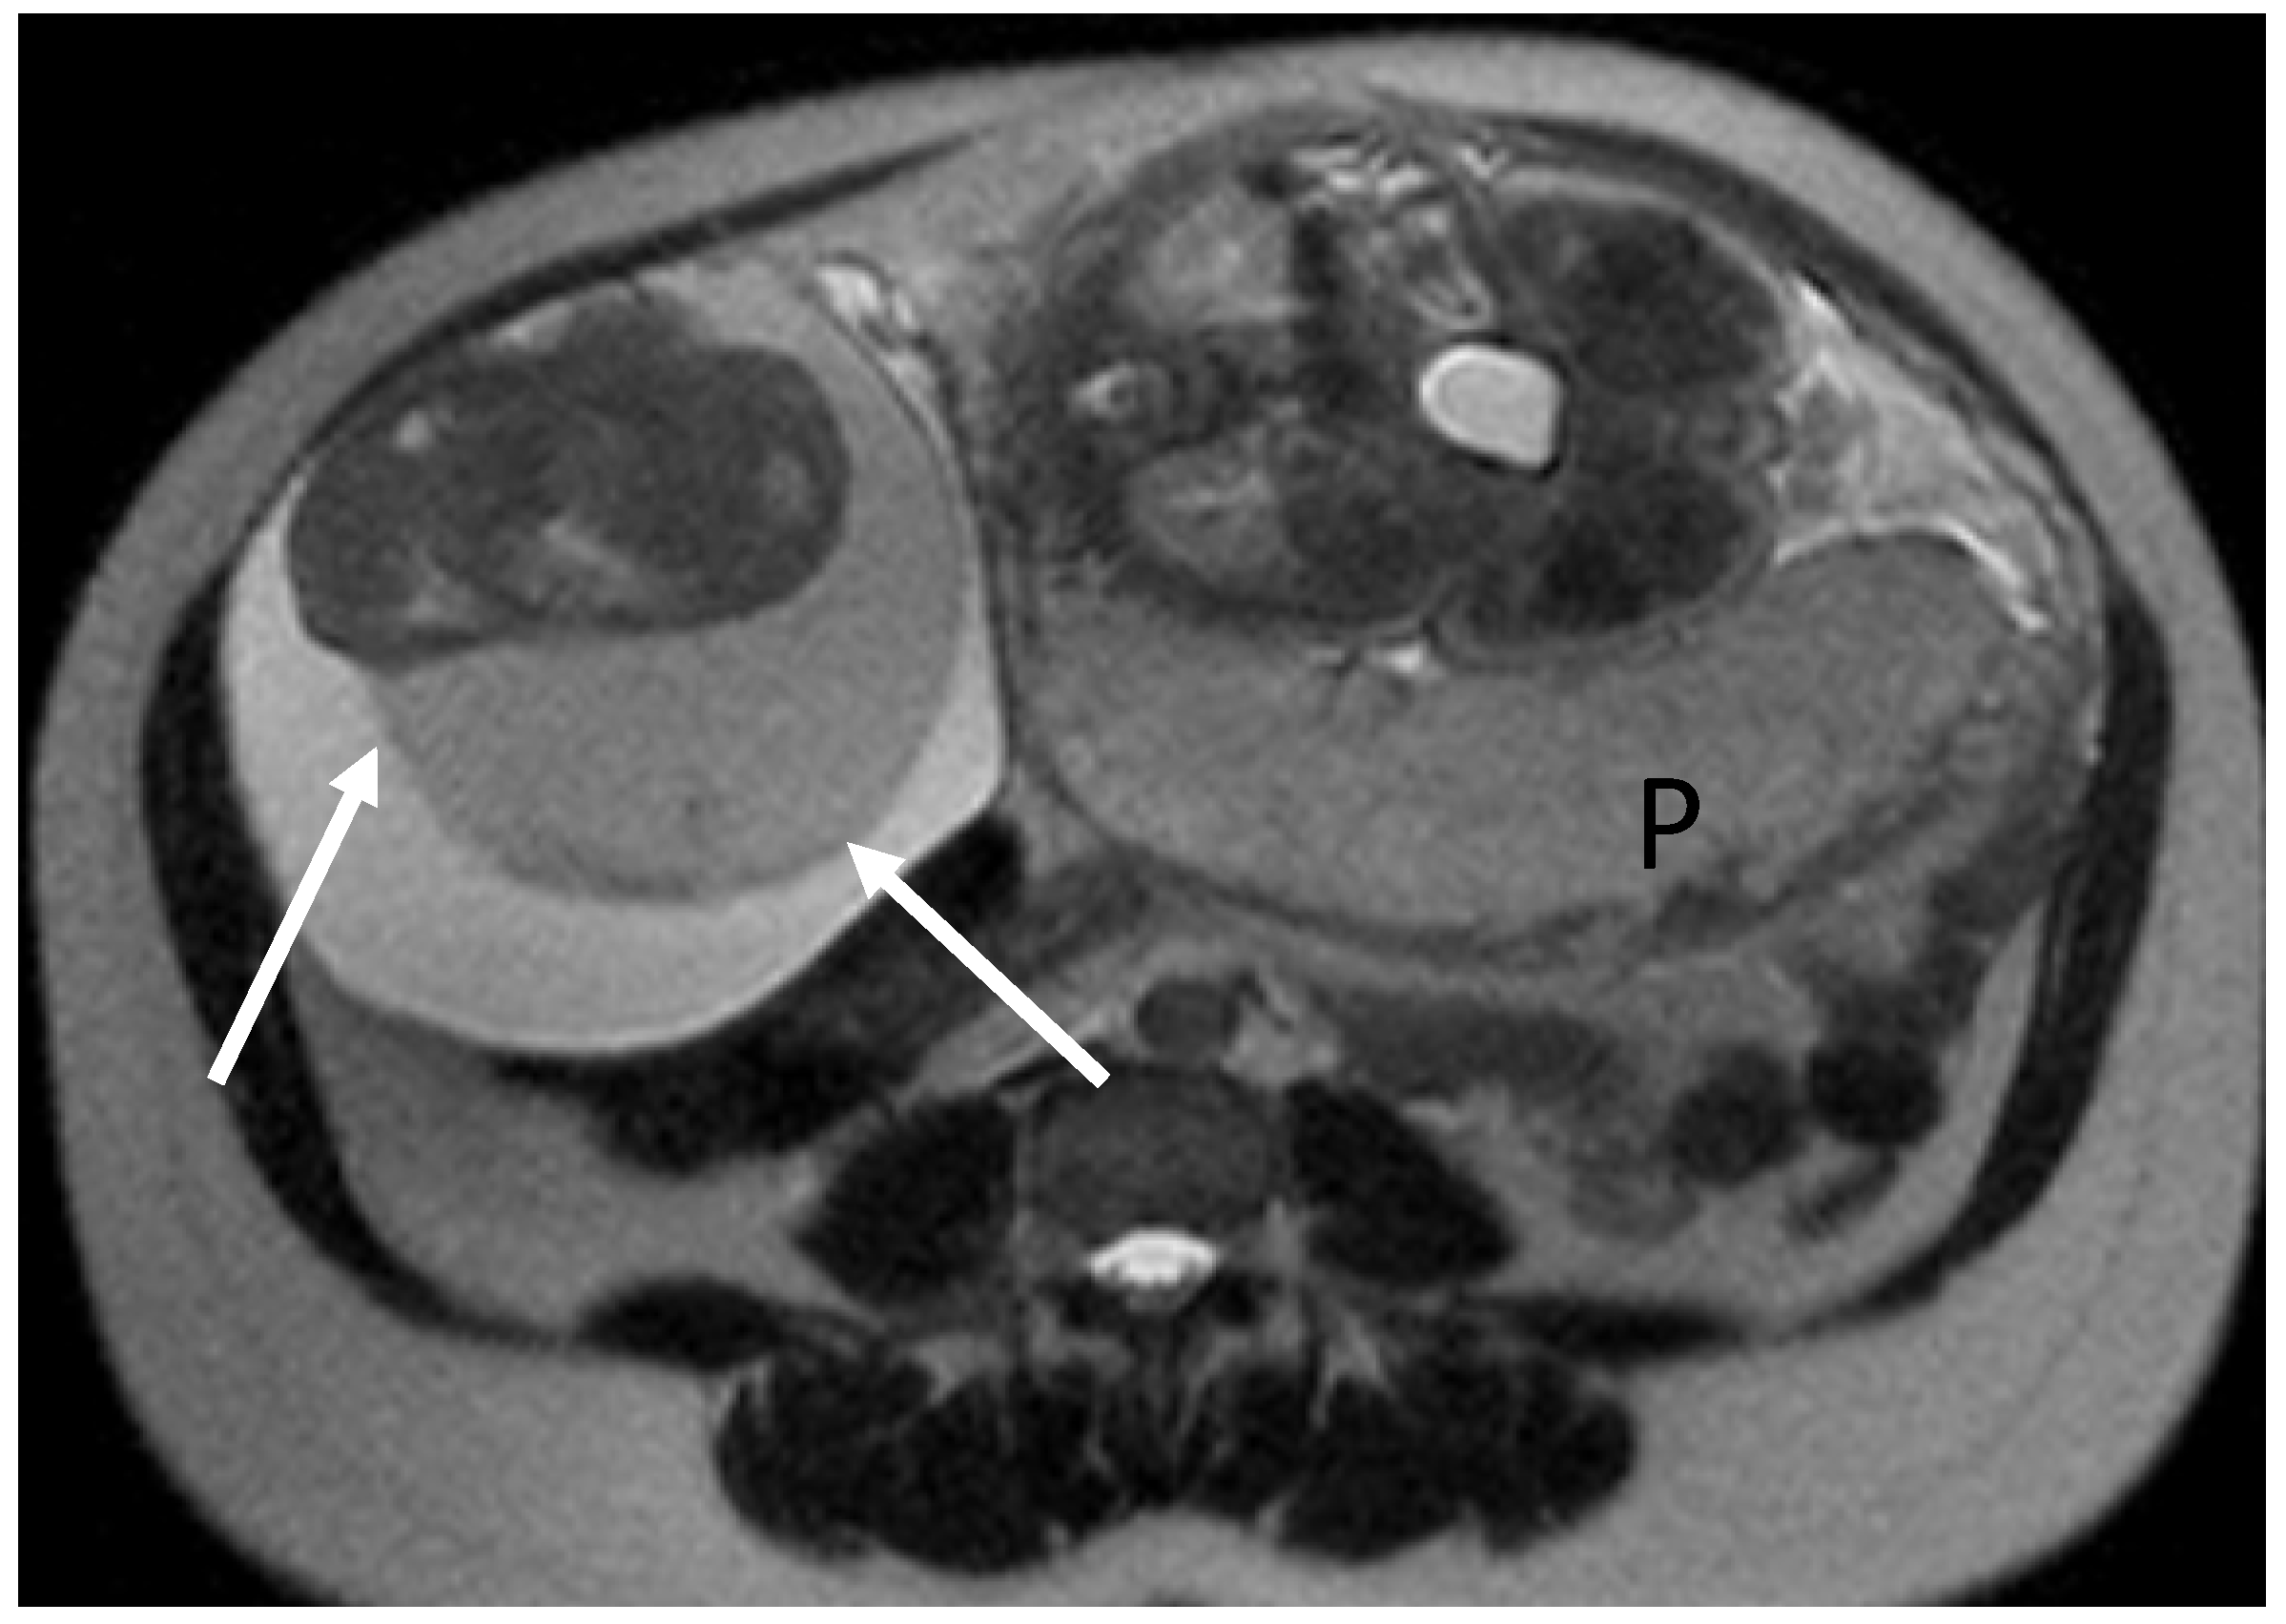

3.4.2. Imaging

- Bourgioti, C.; Konidari, M.; Moulopoulos, L.A. Imaging of Gynecologic Malignancy in a Reproductive Age Female: Cancer During Pregnancy. Radiol. Clin. N. Am. 2020, 58, 413–430. [Google Scholar] [CrossRef]

- Harwin, J.; Jha, P.; Post, A.; Silverstein, J.; Van Loon, K.; Poder, L. The radiologist’s role in a multidisciplinary approach to cancer in pregnancy. Abdom. Radiol. 2023, 48, 1605–1611. [Google Scholar] [CrossRef]